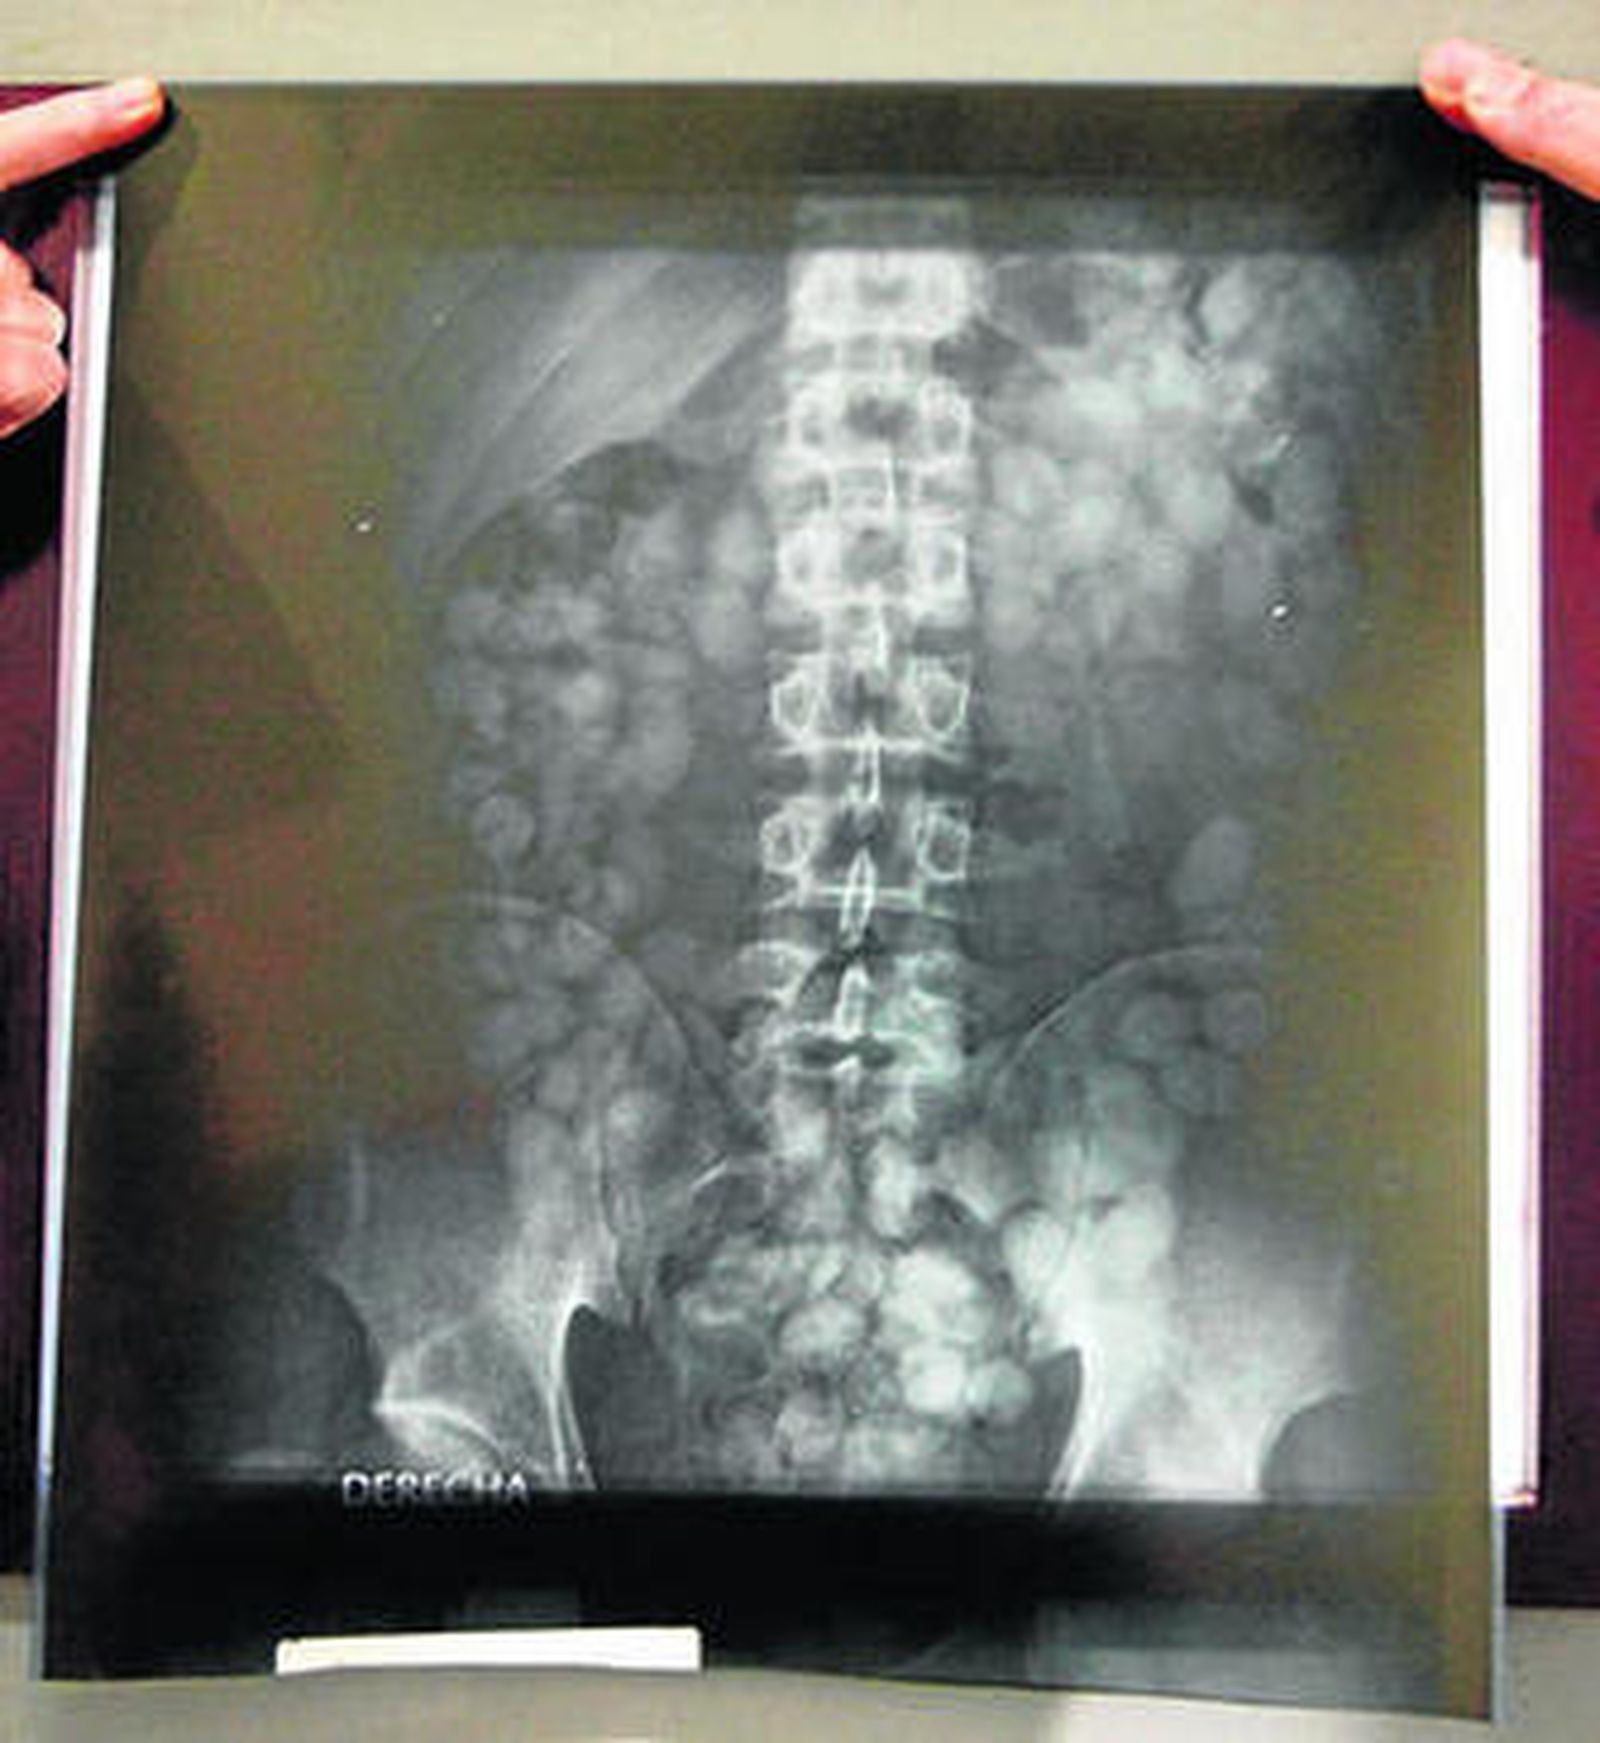

Una radiografía visualiza las bellotas ingeridas.

La Guardia Civil está al tanto de la llegada de los ferrys. Los que llegan de noche son los más utilizados por los pasadores porque normalmente ya no está la ATS, que trabaja en Aduanas. La alarma salta o bien por la pinta que tienen, por el DNI o porque le han visto pasar muchas veces. Entonces los guardias civiles ponen su instinto a trabajar. De hecho, el 90% de las personas sospechosas que son enviadas a hacerse una radiografía llevan droga en el interior de su cuerpo.